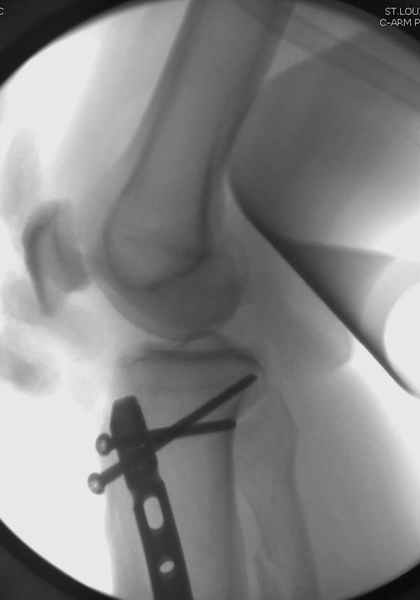

спрашивает что делать с больным который поступил недавно, фермер 55 лет падение при пьяной драке в баре, года два назад перенес операцию на лодыжке, на снимках и КТ перелом без вовлечения сустава,

Повреждение такой локализации, на которой применимы и аппарат (классический Илизарова или гибридный), пластина, особенно Locked Plate, и гвоздь с блокированием. В нашей клинике был бы выполнен закрытый интрамедуллярный остеосинтез. Желательно использовать гвоздь с возможностью провести более чем 2 обычных фронтальных винта в дистальном отломке.

Здесь мы использовали новый Synthes Nail с дополнительными дырками, в проксимальной части 4: по две косых и поперечные (один стандартный а другой динамический), в дистальной части две поперечные, прямая и косая. Вес больного более 120 кг, нагрузку начнем через месяц.

Получилось красиво, поздравляю. Вверху можно было ограничиться одним винтом во фронтальное статическое отверстие, зачем два 45-градусных?

При такий спирали задний край tibia может быть сломан - нет ли этого в данном случае? На всякий случай можно было ввести 1-2 винта 4,5 мм спереди назад мимо гвоздя. Хотя самый дистальный блокирующий винт, возможно, зацепил этот отломок. А какой тут диаметр гвоздя и locking винтов?